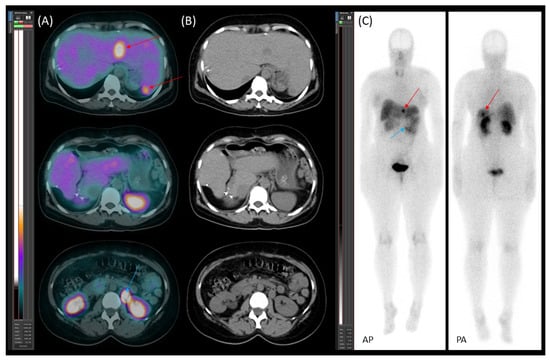

On 30 November 2020, [99mTc]Tc-EDDA/HYNIC-TOC somatostatin receptor scintigraphy with SPECT/CT was performed using a native, low-dose protocol. Oral contrast (1000 mL of polyethylene glycol solution) was administered 60 min prior to imaging to promote bowel distention without introducing contrast material-induced attenuation correction artefacts. The imaging revealed increased radiopharmaceutical uptake in CT-identified lesions, consistent with somatostatin receptor expression (Figure 1). Serum chromogranin A (CgA) levels were moderately elevated at 108 ng/mL (reference range: 19.0–98.0).

Figure 1. [99mTc]Tc-EDDA/HYNIC-TOC scintigraphy with SPECT/CT. (A) Transaxial SPECT/CT, (B) transaxial CT, and (C) planar images (AP—anteroposterior; PA—posteroanterior) demonstrate somatostatin receptor (SSTR)-positive lesions. Multiple metastatic liver lesions are visible in all modalities (red arrows). The primary lesion in the pancreatic tail is clearly identified on the SPECT/CT image and is marked with a white arrow.